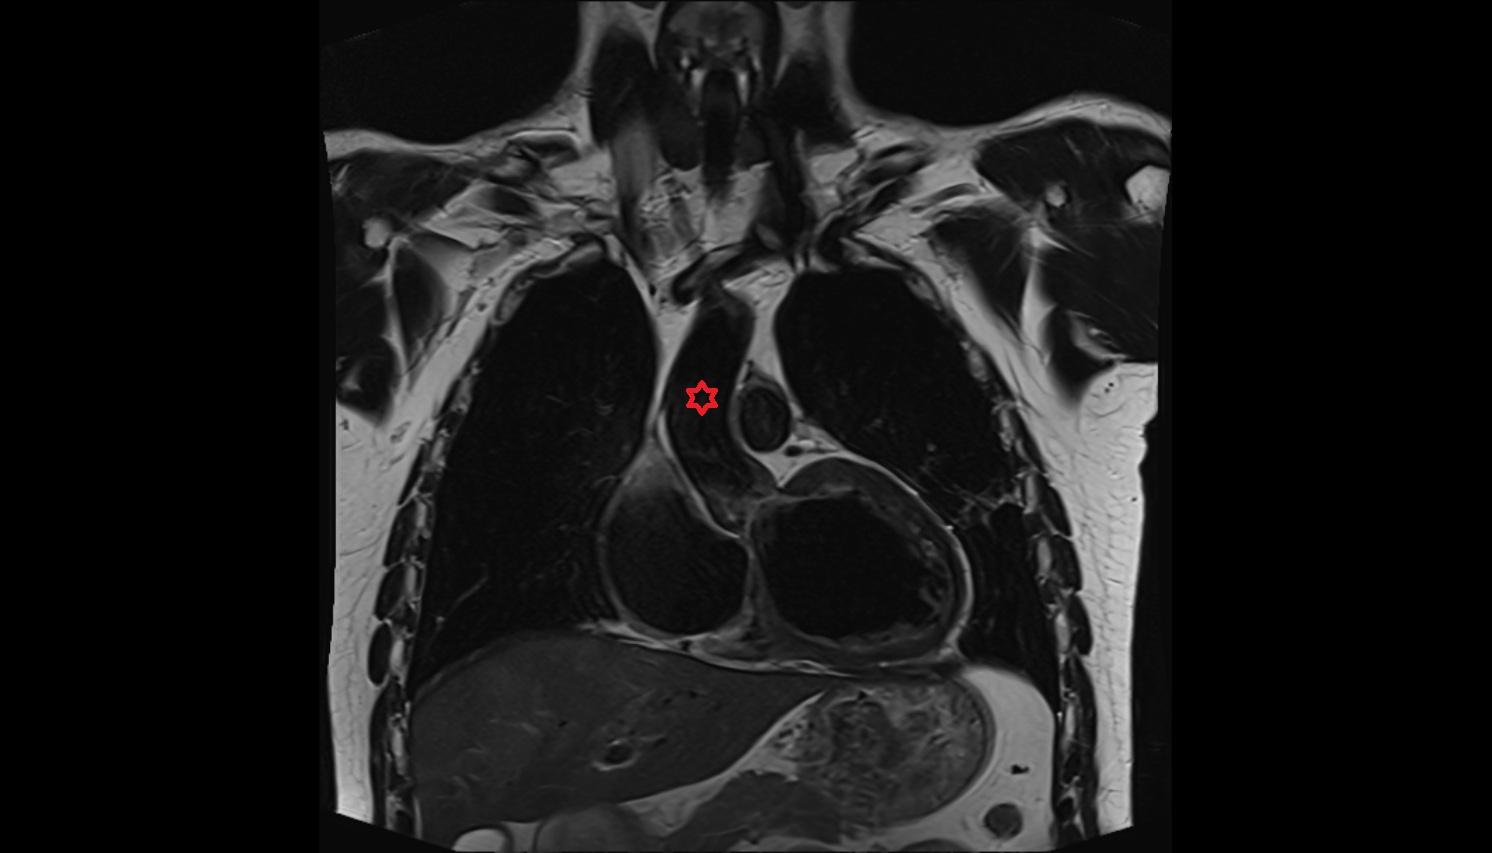

- Pericardium

- Heart

- Left atrium

- Pulmonary trunk

- Ascending aorta

- Arch of aorta